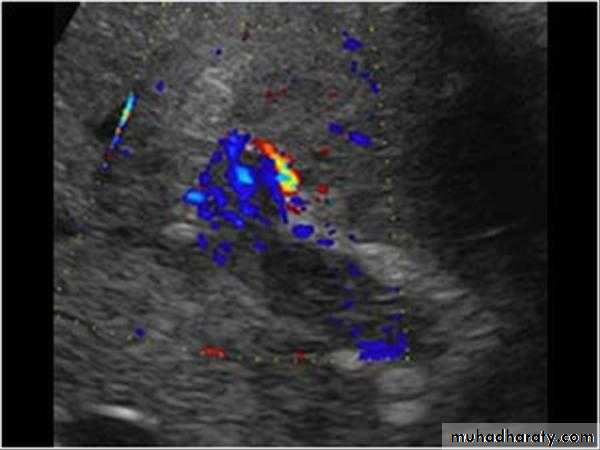

Cirrhosis & portal hypertension